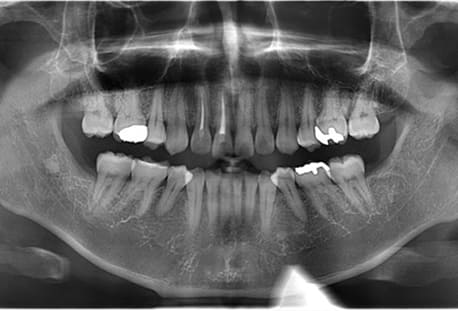

Case01

- 原因

- 水平埋伏智歯

- 治療内容

- 下顎の水平埋伏智歯を抜歯

<リスク・副作用>

手術後は痛み、腫れ、痺れなどの副作用が生じる場合があります。